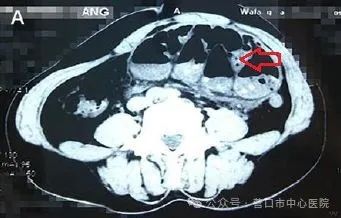

近期,市中心医院普外三科接诊了一位特殊的腹痛患者。患者赵大爷,因腹部肿块疼痛伴停止排气排便1天来院就诊。腹部CT结果显示:左中下腹小肠积液并扩张,并肠壁水肿。考虑肠梗阻腹内疝。腹部查体:腹肌紧张,左中下腹压痛阳性,腹肌紧张,左下腹可触及包块,约10 cm×8 cm,质硬,活动度差。接诊的张博医生考虑到患者腹痛剧烈,结合体格检查及腹部CT检查,不排除腹内疝可能。于志勇主任全面细心向患者家属说明病情后,建议急诊手术,以防肠坏死发生。

患者的腹部CT,红色箭头为扩张的肠管